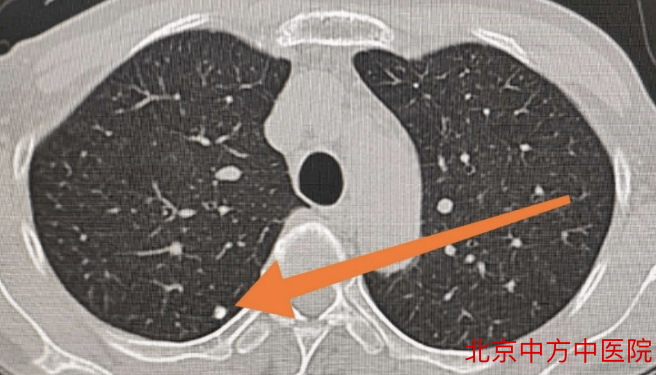

根据胸部CT判断是否存在磨玻璃密度成分,可将肺结节分为:磨玻璃结节、实性结节和混合结节。

(1)磨玻璃结节

磨玻璃样结节是指肺内密度轻微增加,呈模糊的云雾状,但仍能通过病灶看到其内部血管和支气管纹理,就好像透过磨玻璃观察一样。

(2)实性结节

实性结节是指肺内圆形或类圆形高密度阴影,在CT下呈现白色的影子。实性结节,表面光滑小而圆的,多属于良性。

(3)混合结节

即部分磨玻璃,部分实变的结节,被称为“最可怕的结节”,恶性率通常在60%以上。